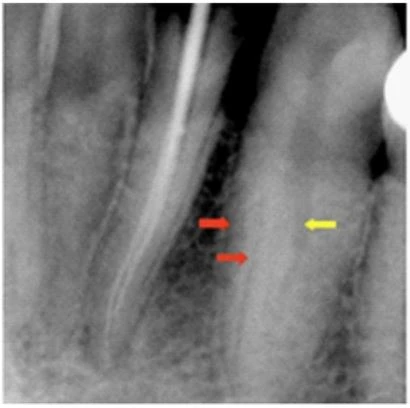

– Nhìn trên phim X-quang có 1 đường song song với lamina dura (mũi tên màu đỏ). Dấu hiệu này gợi ý tiết diện chân răng hình số 8(hình 1.1).

– Ống hẹp bất ngờ (mũi tên vàng) lưu ý cần phân biệt với các ống tủy bị canxi hóa(hình 1.1).

– Chụp phim đo chiều dài hay thử cone. Sẽ thấy cây trâm hoặc câu cone không nằm chính giữa ống tủy mà lệch qua 1 bên(hình 1.2)